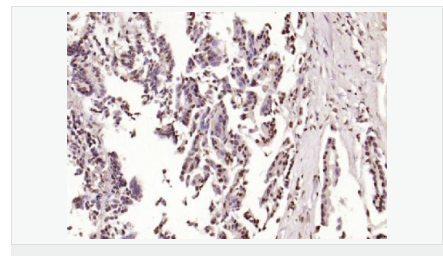

交叉反应:Human,Mouse,Rat(predicted:Dog,Pig,Rabbit,GuineaPig) 推荐应用:IHC-P,IHC-F,ICC,IF,Flow-Cyt,ELISA

| 产品应用 | ELISA=1:5000-10000 IHC-P=1:100-500 IHC-F=1:100-500 Flow-Cyt=1μg/Test ICC=1:100 IF=1:100-500 (石蜡切片需做抗原修复) not yet tested in other applications. optimal dilutions/concentrations should be determined by the end user. |